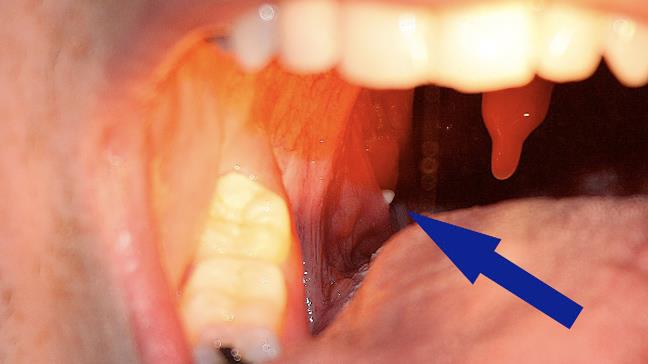

Although your tonsils can keep you healthy, they sometimes get infected with the very same bacteria when the load is too much. Tonsils actually consist of lymphocyte tissue which is the infection fighter of the body. The tonsil is made up of a spongy texture which according to doctors can also be a breeding ground for tonsil stones. The condition is called tonsilloliths where little hard growths start appearing on the tonsils.

On the surface texture of the tonsils, there are several dips and crevices which tend to trap food and mucus. This then attracts bacteria that get entrenched in it. The continuous formation of such occurrence causes the formation of a hard ball called a tonsil stone. In effect, it is a consequence of your body’s protection from the bacteria. Thus in trying to protect your body from food mixed with bacteria, your tonsils form these little-calcified globs.